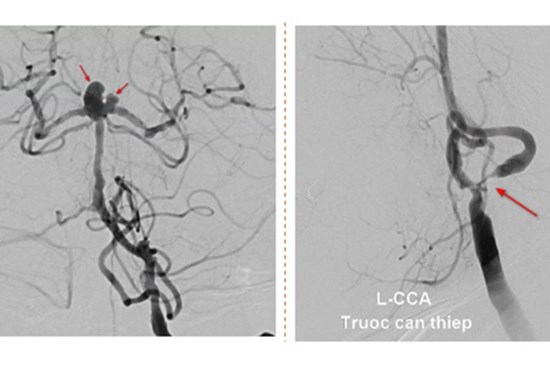

Người phụ nữ bị cùng lúc 2 dạng đột quỵ đặc biệt nguy hiểm

Nhập viện với chẩn đoán bị nhồi máu não bán cầu trái, yếu liệt nửa người. Qua kiểm tra hình ảnh, bác sĩ phát hiện ngoài tình trạng bị nhồi máu não, bệnh nhân còn có nguy cơ vỡ túi phình dẫn đến xuất huyết não.